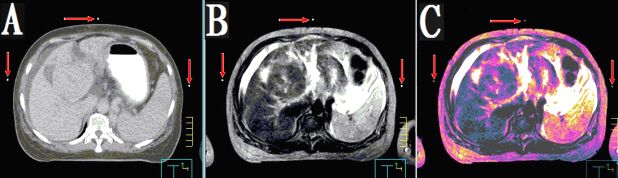

本產(chǎn)品主要適用于不同模態(tài)圖像引導下放療時定位,定點經(jīng)皮穿刺活檢或積液抽吸引流,不同模態(tài)間圖像融合控制點配準等。

3.??同一定位貼,在多種模態(tài)掃描下成像均能顯示為點狀,可用作圖像融合的共同配準控制點,大小、位置一致,方便全身或軀段臟器異機圖像融合,精度高,易開展新的臨床應用。

CT和MR通用型:具有同一個定位球在CT掃描高密度、MR常規(guī)掃描高信號的特點,主要用于

CT/MR圖像融合,更換掃描設備,不需要更換標記點。型號MK⊙CT/MR,每盒三貼;